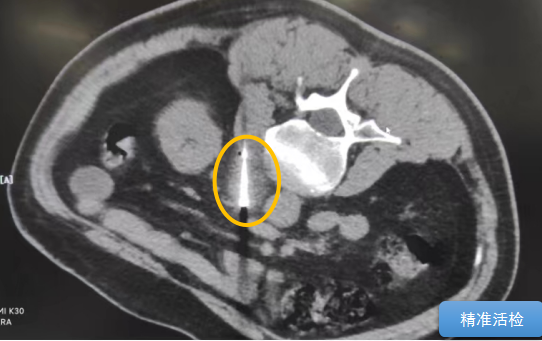

經過多學科討論,陳寶瑩主任根據(jù)影像資料指出,患者轉移瘤位于腹膜后,內側瀕臨人體最大的血管——主動脈;前方同樣有血管緊貼腫瘤;外側是腎臟,后方是椎體和神經,夾縫中進針難度大,治療時要避免周圍重要臟器、血管和神經的損傷,因此可以選擇CT引導下精準穿刺活檢同步冷凍消融治療,即獲得病理組織有利于下一步全身治療方案的調整,同時殺死腹膜后轉移瘤,周圍正常組織損傷的可能性也小。

術中陳寶瑩主任、李鐵柱教授、兀云飛醫(yī)生、魏東紅技師、汝平護士協(xié)調配合,夾縫進針難度雖大,但在CT引導下逐步進針,精準到位,順利活檢取得組織,由于腫瘤較大,為了提高消融效率,平行置入兩根冷凍消融針,同時啟動冷凍消融,術中清晰觀察到冰球完全覆蓋病變,患者沒有任何不舒服,治療中還可以和醫(yī)生聊天。